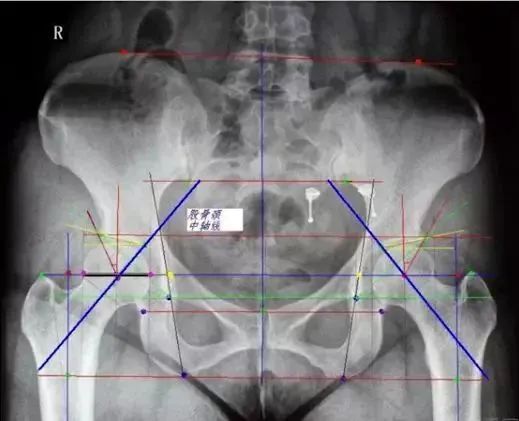

如何从一张普通骨盆片中获取足够信息

股骨模板测量:

①选择骨盆正位片与合适比例模板;

②股骨距应与模板上的股骨距部相吻合;

③对应颈长的中心应与股骨头中心相吻合;

④经过假体中心的横线应与大粗隆顶点相切;

⑤填充髓腔,注意股骨距的高度。

髋臼模板测量:

②将模板按照45°倾斜角度放入髋臼;

③估计锉后髋臼的大小,内壁的厚度;

④假体的大小应与软骨下最少的截骨量一致;

⑤假体的中心与原髋臼的旋转中心尽可能一致。